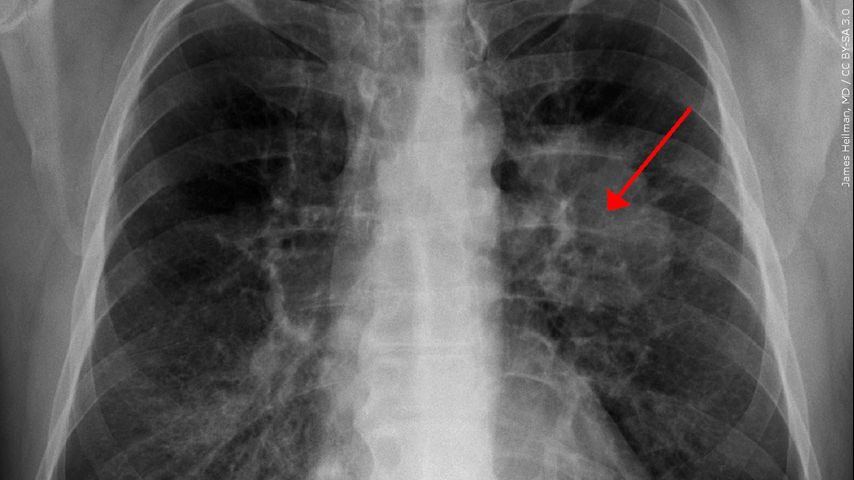

Most health organizations recommend a yearly test using a Low-Dose CT (LDCT) scan.

The Centers for Disease Control and Prevention (CDC) explains that during the scan, the patient lies on a table while an X-ray machine uses a low amount of radiation to create detailed images of their lungs. The entire scan is not painful and typically takes only a few minutes.